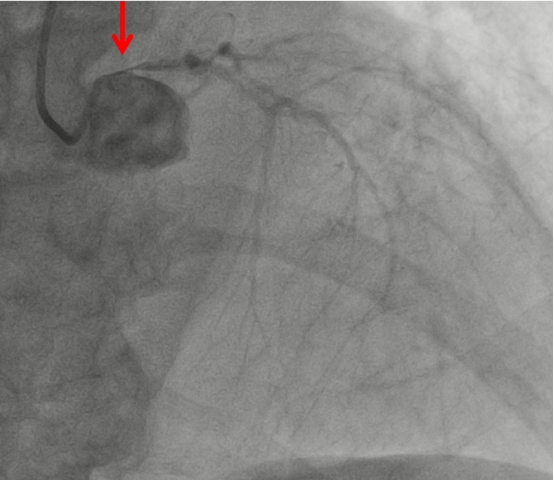

10月24日凌晨1时,67岁的姜大叔突发胸痛并持续加重,伴有大汗,在家忍受了4小时后才拨打了120电话送到我院,经绿色通道行急诊冠脉造影见:右冠急性闭塞、左主干重度狭窄、前降支中远段慢性闭塞、回旋支近段重度狭窄。一边血管堵塞一边血管开口接近闭塞,相当于心肌只有很少血液供应,随时有猝死风险。

图1:右冠闭塞